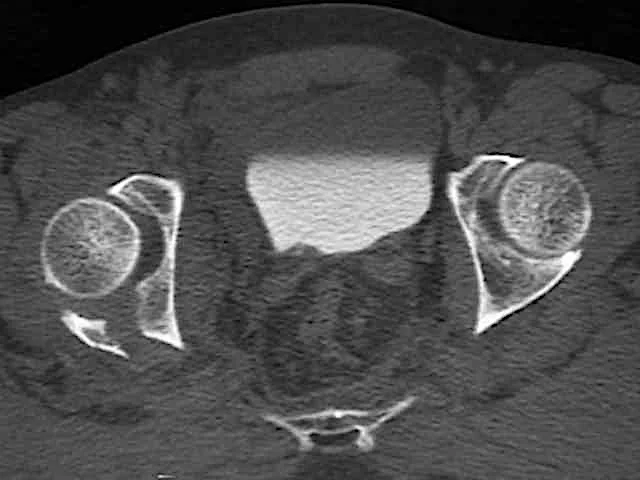

- CT Scan:

- In complex and intra-articular fractures

- In spine

- In pelvic and acetabular fractures

- In calcaneal fractures